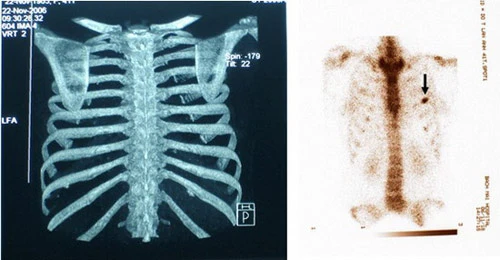

Các bác sĩ sẽ tiến hành rút bỏ xương sườn thứ 11 và 12.

Các chuyên gia cũng có thể rút bỏ xương sườn số 10 theo yêu cầu của bệnh nhân để tạo 1 khoảng trống nhằm định hình vòng 2 siêu nhỏ.

Ngoài ra, khi xương sườn số 11 và 12 bị loại bỏ thì có nghĩa bạn chỉ được bảo vệ từ phía sau. Bạn sẽ khiến những bộ phận quan trọng trong cơ quan nội tạng như gan, thận và một phần của dạ dày không có bộ khung để bảo vệ...